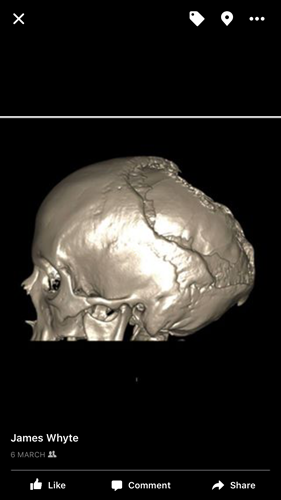

Above is pictures of Sarah's skull were Gorhams is present. Its also known as a bone vanishing disease which is quite clear on that picture.